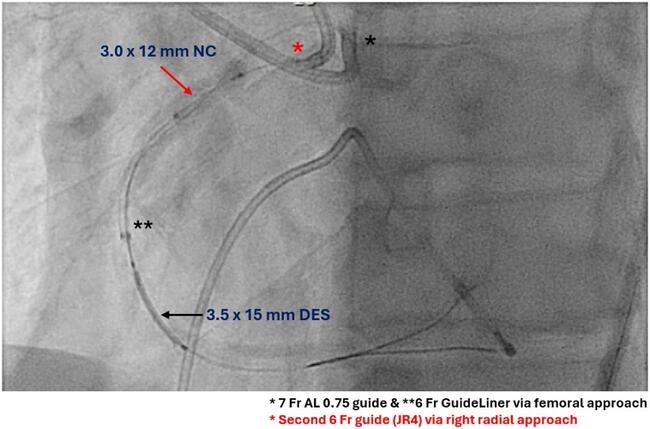

Video 1. Successful passage of a 3.5 x 15-mm drug-eluting stent using modified “tunnel-in-landslide” technique (TILT).